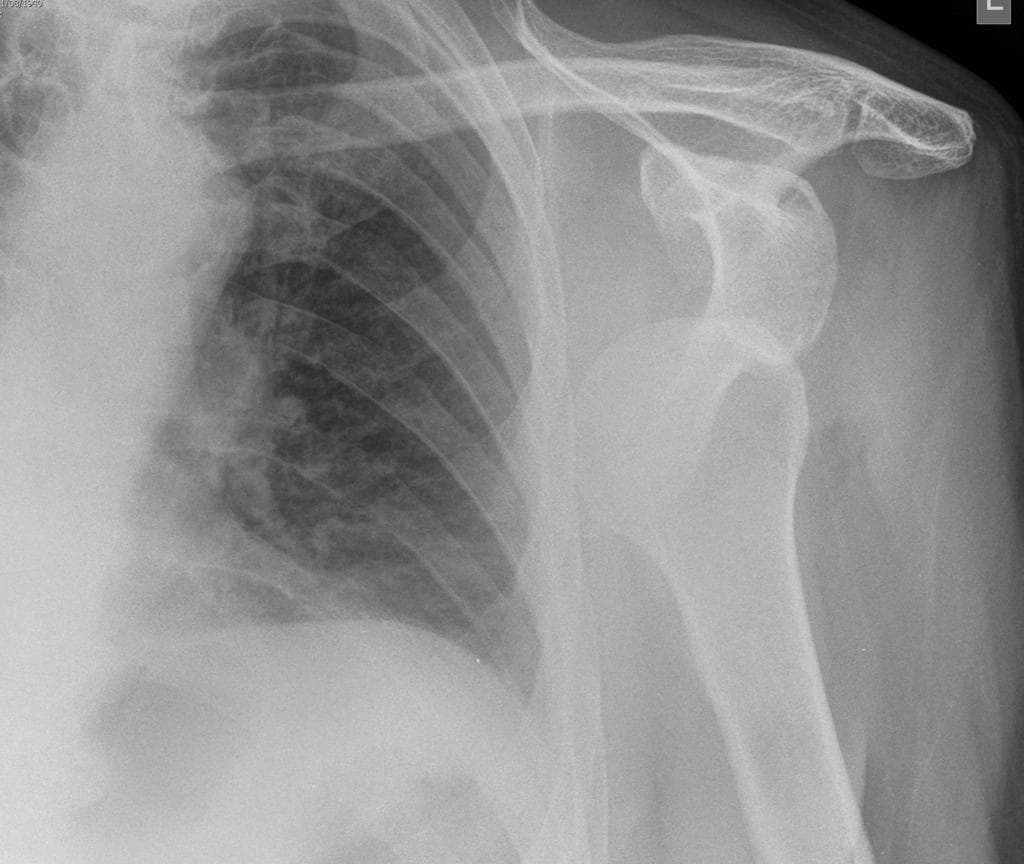

Lateral

X-ray•Lateral•1 Img

Ca bệnhTrật khớp vai ra trước

Trật khớp vai ra trước

Trật khớp vai ra trước. Trục khớp ổ chảo - cánh tay bình thường. Không thấy trật khớp. THẢO LUẬN: Hình ảnh X-quang khớp vai phải cho thấy tình trạng trật khớp ra trước, đã được nắn chỉnh thành công.